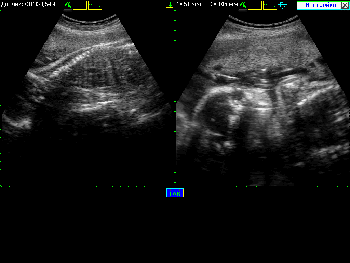

Примеры того, как выглядит экран при различных режимах сканирования можно увидеть в Таблице 4.

Таблица 4. Общий вид экрана в различных режимах сканирования.

| Вид экрана | Режим сканирования |

|---|---|

![]() |

Режим В+М |